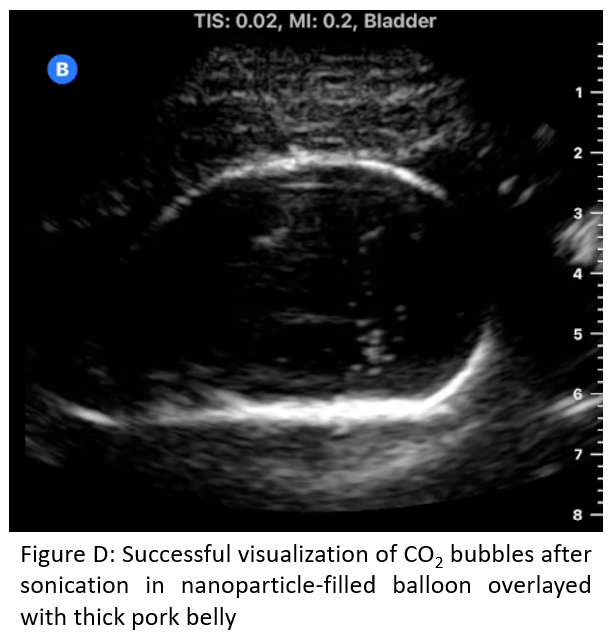

Results: Figures B and C show the nanoparticle and water solutions upon stimulation with ultrasound, respectively in the balloon-only model. Our work demonstrates the potential to produce and visualize microbubbles when applied to CO2-loaded nanoparticles. Additionally, visualization was successful with a 37 mm thick layer of pork belly interposed between the ultrasound and balloon (Figure D).

Methods: Polyethylenimine (PEI, 500-940 mg) was dissolved in solvent (DI water, ethylene glycol, or PBS; 10 mL), followed by addition of dry ice (50 g) as a CO2 source in a sealed Parr apparatus. Dry ice released CO2 and the reaction was stirred for 18 hours until it reached ambient temperature. A rubber balloon (simulating a bladder) was filled with either water only or the nanoparticle solution (Figure A). We used a prototype 1.1 MHz spherically focused, air-backed transducer (focal depth: 55 mm) or a prototype unfocused 1.66 MHz air-backed transducer, a computer-controlled RF generator (JJ&A Instruments) to provide bubble sonication, and a Butterfly iQ imaging system to simultaneously visualize the bubbles produced. We used an electrical power of 10 W with 10% duty cycle (1 ms on, 9 ms off) for a period of 5 seconds. Following this, a 37mm layer of pork belly was interposed between the ultrasound transducers and the experiment repeated.